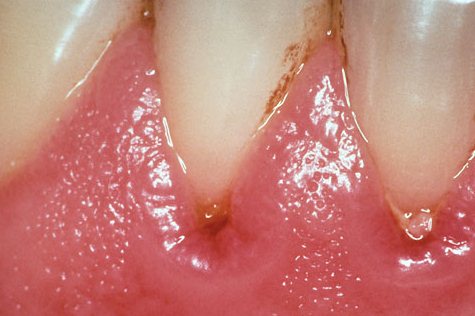

Внешне гингивит диагностируется следующими признаками и симптомами: десна имеют цвет от бледно- до ярко-красного, отечны, может быть наличие язвочек, которые заживая, образуют гипертрофированную ткань, которая нависает над зубом. Хотя соединение между десной и зубом не нарушено, кажется, что плотное прилегание десны к зубу отсутствует.